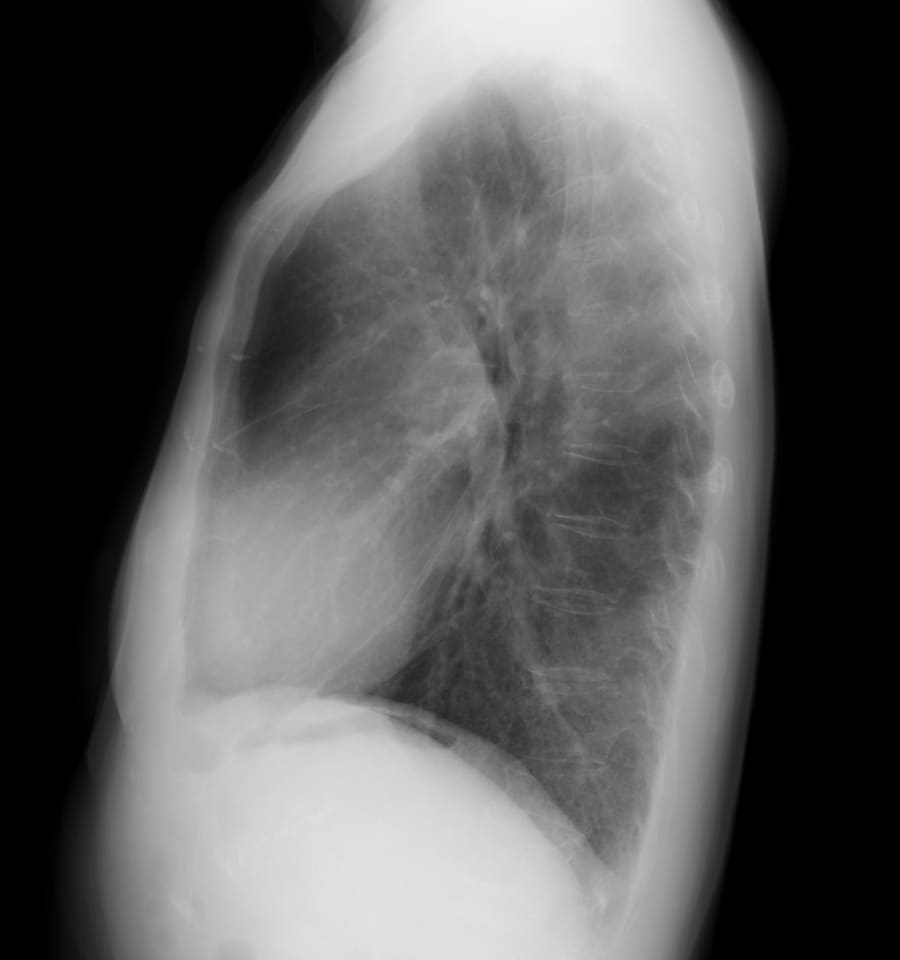

DATA 1| X 線検査結果

画像にマウスオン(またはタップ)すると虫眼鏡で拡大できます